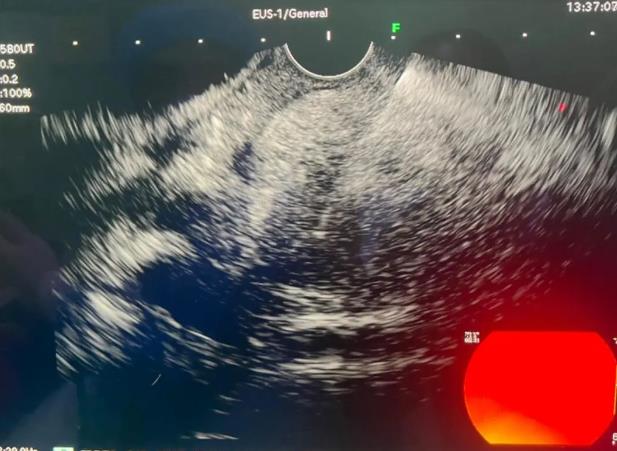

患者,女性,44岁,以“上腹部疼痛不适1周”入院,腹部CT及MRI提示胰头钩突-十二指肠水平部结节,考虑神经内分泌肿瘤可能性大,胰头周围多发淋巴结转移; EUS提示胰腺钩突部可见一0.9*0.7cm大小实性占位,行EUS-FNB病理结果回归提示神经内分泌瘤(NET G1)。